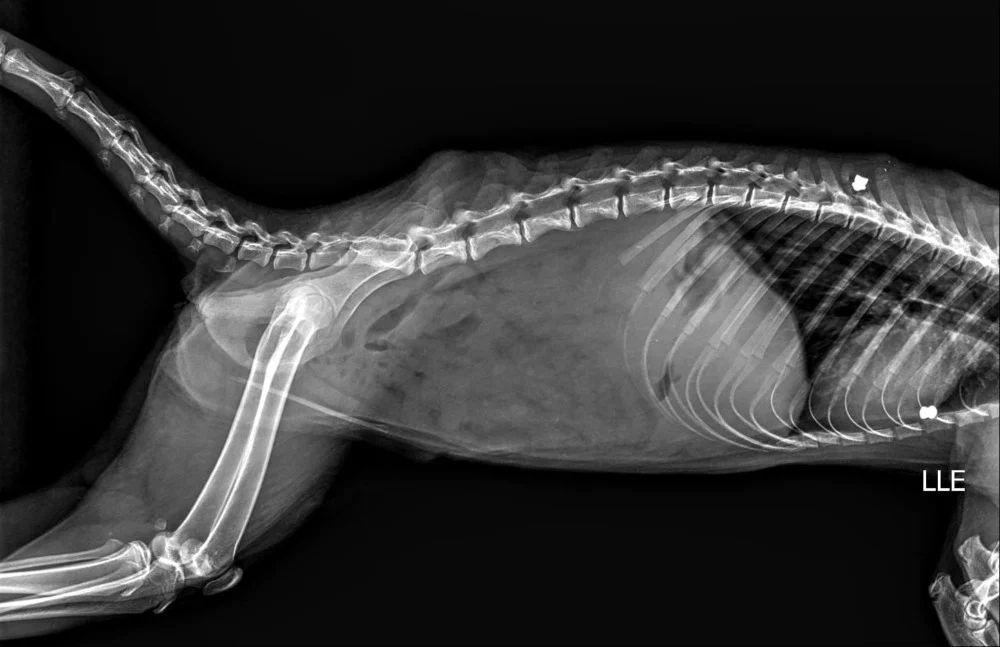

Um dos casos mais alarmantes envolve uma fêmea de quati que apresentava projéteis alojados em seu corpo, inclusive na região da coluna vertebral. A médica veterinária Melissa Campitelli, após realizar um raio-x em um dos animais, confirmou a presença de dois chumbinhos em seu organismo, evidenciando a crueldade com que os quatis estão sendo tratados.